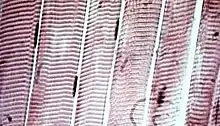

![]() The body contains three types of muscle tissue: (a) skeletal muscle, (b) smooth muscle, and (c) cardiac muscle. (Same magnification) | |

Vertebrate skeletal muscle tissue is an elongated striated muscle tissue with the fibres ranging in width from three to eight micrometers and in length from 18 to 200 micrometers. In the uterine wall during pregnancy they enlarge in length from 70 to 500 micrometers.[3] Skeletal striated muscle tissue is arranged in regular, parallel bundles of myofibrils containing the many contractile units known as sarcomeres, which give the tissue its striated (striped) appearance. Skeletal muscle, is voluntary muscle anchored by tendons or sometimes by aponeuroses to bones, and is used to effect skeletal movement such as locomotion and to maintain posture. Postural control is generally maintained as an unconscious reflex, but the muscles responsible can also react to conscious control. An average adult man is made up of 42% of skeletal muscle as a percentage of body mass, and an average adult woman is made up of 36%.[4]